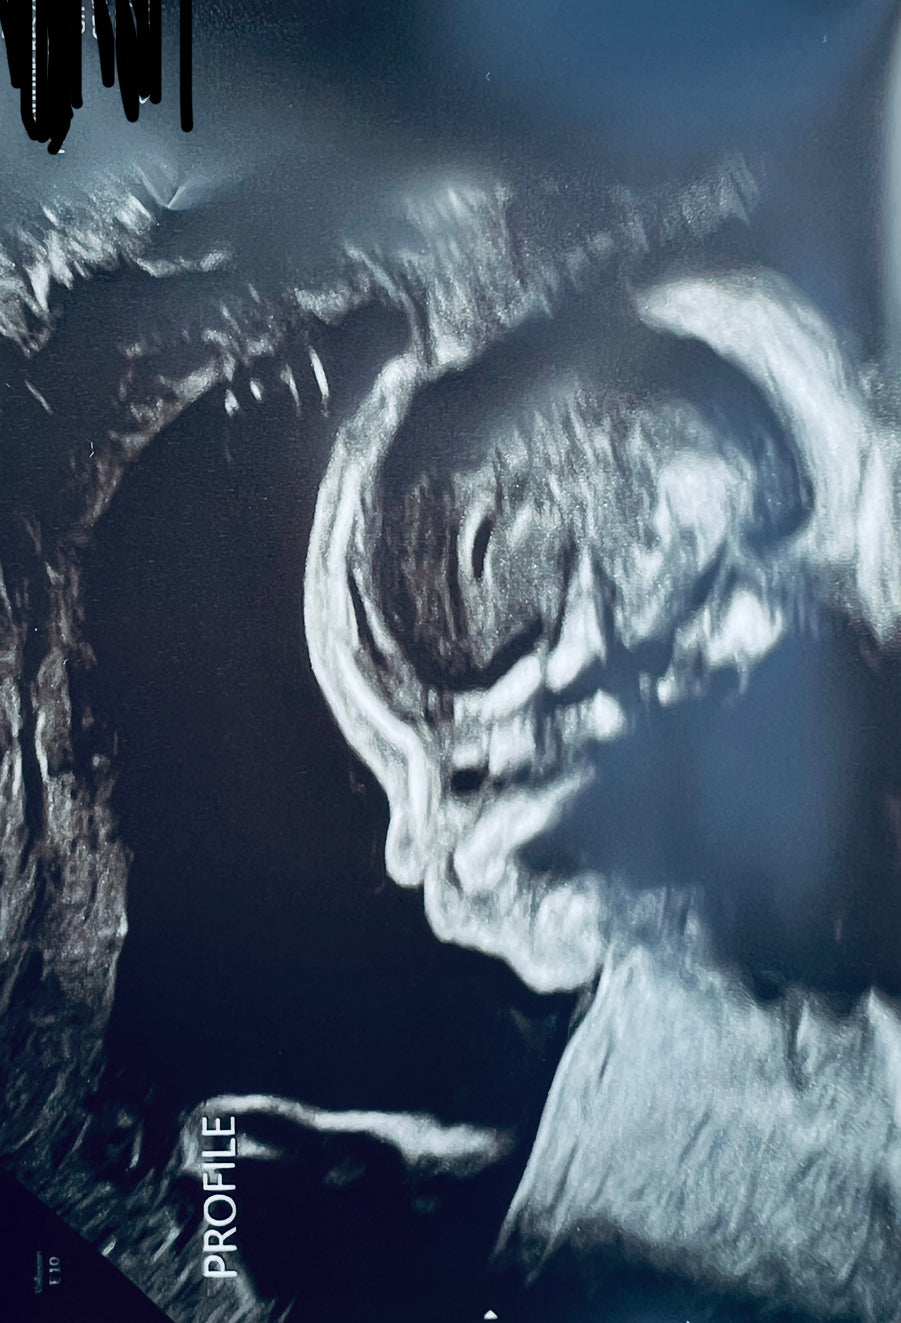

My husband and I had been hoping to get pregnant for years. Finally last year we decided we needed to really go into full baby making mode. It’s very stressful when it doesn’t just happen right away. We took tests everything was normal. So we used mosie in addition to our regular activities and got pregnant with in 6 months. It definitely helped take off some of the pressure.